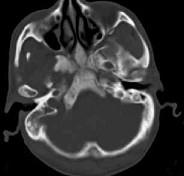

男性,56岁,鼻咽癌放疗后复查,CT扫描如图所示,请选择正确的答案()A.化脓性骨髓炎B.骨结核C.致密性骨炎D.放疗后骨炎E.骨瘤

问题 男性,56岁,鼻咽癌放疗后复查,CT扫描如图所示,请选择正确的答案()

选项 A.化脓性骨髓炎 B.骨结核 C.致密性骨炎 D.放疗后骨炎 E.骨瘤

答案 D